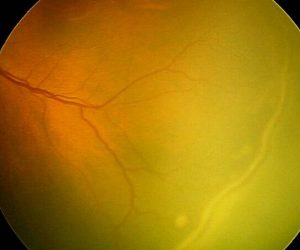

Retinopathy of prematurity (ROP) is an ocular condition that can occur in premature infants. It prompts the development of abnormal blood vessels in the retina, potentially resulting in blindness.

Retinopathy of prematurity involves the abnormal growth of blood vessels in the eye, which can result in leakage or bleeding. This process leads to the formation of scars on the retina, the nerve tissue layer responsible for transmitting light-related messages to the brain.

As these scars contract, they may exert tension on the retina, causing it to detach from the rear of the eye. In severe instances, this can culminate in vision impairment and, in extreme cases, blindness.